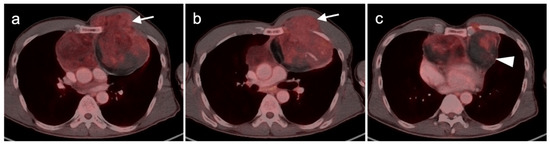

- Camoni, L.; Albano, D. Contrast-enhanced 18F-FDG PET/CT to differentiate primary cardiac lymphoma from primary cardiac angiosarcoma. J. Nucl. Cardiol. 2021, 1–3. [Google Scholar] [CrossRef]

- Umemura, H.; Yamasaki, O.; Kaji, T.; Hamada, T.; Otsuka, M.; Asagoe, K.; Iwatsuki, K. Prognostic value of 18 F-fluorodeoxyglucose positron emission tomography/computed tomography in patients with cutaneous angiosarcoma: A retrospective study of 18 cases. J. Dermatol. 2017, 44, 1046–1049. [Google Scholar] [CrossRef] [Green Version]

- Tokmak, E.; Özkan, E.; Yağcı, S.; Kır, K.M. F18-FDG PET/CT Scanning in Angiosarcoma: Report of Two Cases. Mol. Imaging Radionucl. Ther. 2011, 20, 63–66. [Google Scholar] [CrossRef]